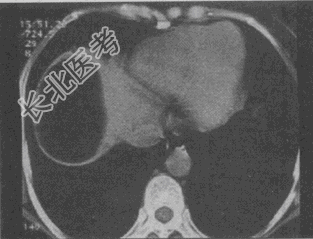

- 单项选择题患者男,30岁, 右下腹稍隆起,CT检查如图, 最可能的诊断为

A、右膈下脓肿

B、间位结肠

C、右膈下脂肪瘤

D、右下肺肺大疱

E、右下肺炎